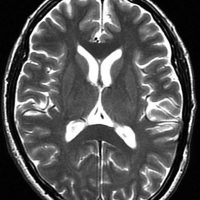

肺小細胞癌の転移 multiple metastases of lung small cell cancer

左のMRIは,肺小細胞癌の患者さんに脳転移が無いか確かめるために撮影されたものです。転移はありませんでした。右側のMRIは,そのわずか3週間後に撮影したものです。数十個の脳転移がありました。肺小細胞癌では短期間の間に無数の脳転移を生じることがあります。かつては脳転移を予防するための予防的全脳照射という治療が行われていたくらいです。